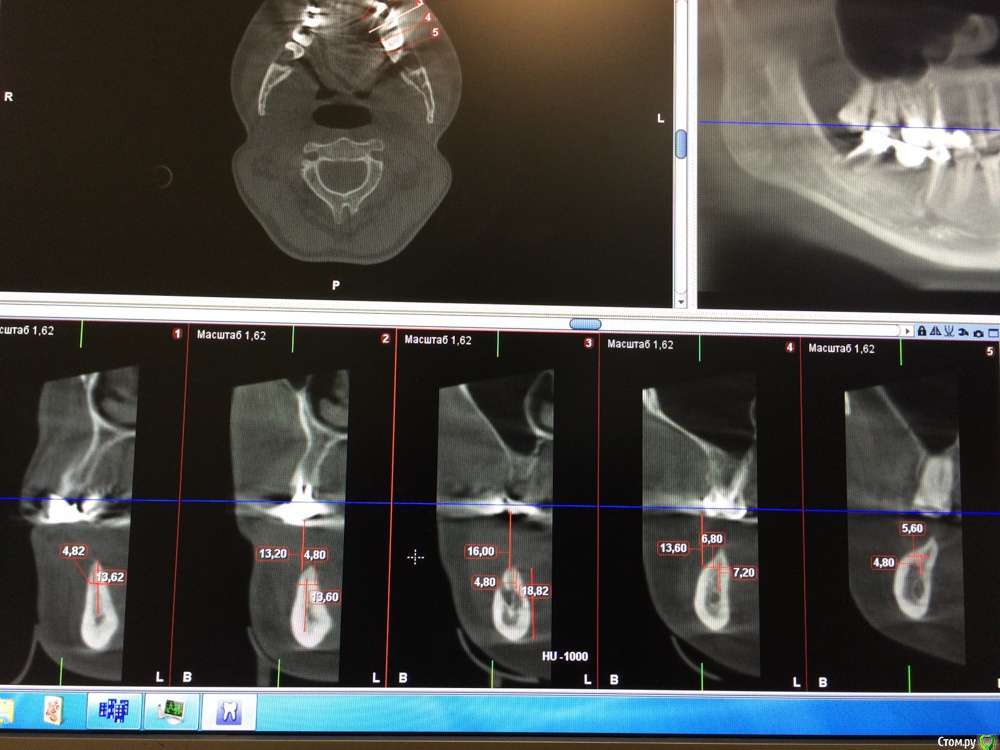

Игнатович Опубликовано 5 марта, 2015 Автор Поделиться Опубликовано 5 марта, 2015 (изменено) КТ36 лет... хронических заболеваний не выявлено, недавно проходила обследование у терапевта Изменено 5 марта, 2015 пользователем Игнатович Ссылка на комментарий